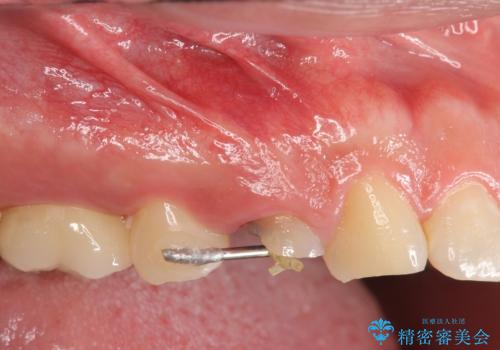

- 上の歯が大きく欠けたとのことで来院されました。

検査の結果、虫歯が大きくなりすぎたせいで薄くなった歯が欠けてしまった経緯が考えられました。

レントゲン画像上で歯茎の深いところまで虫歯になっており、保険治療では抜歯適応になってしまいます。

初診時の状態では虫歯が大きすぎて取り切ることができなかったため、まず歯を骨から引きあげて虫歯がしっかり除去できる状態にしました。